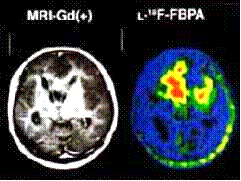

Глиобластома Астроцитома

Рисунок 18 - Диагностика опухолей головного

мозга